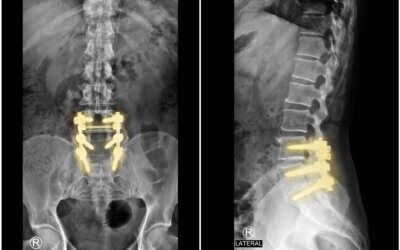

Failed Back Surgery: What Are Your Options? If you continue to experience pain after back surgery, your options may include conservative care, targeted rehabilitation, spinal cord stimulation, revision surgery, or carefully selected non-surgical spinal decompression. The right choice depends on the cause of persistent pain and imaging findings. INTRODUCTION Being told you need a second … Continue reading Failed Back Surgery Options